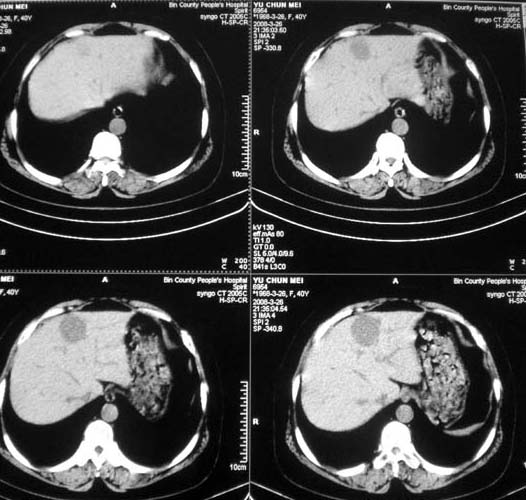

女,56岁,和上两个是同一病人,腹痛,胀痛,消化不良,五年前有血管瘤。密度减低影ct值为40hu。

肝脏血管瘤.

肝脏血管瘤.境界清楚,以前已确诊,没有必要增强吧?

多发性血管瘤!

肝内多发低密度影,边缘清楚,结合病史考虑:肝血管瘤可能性大,建议必须时增强扫描。